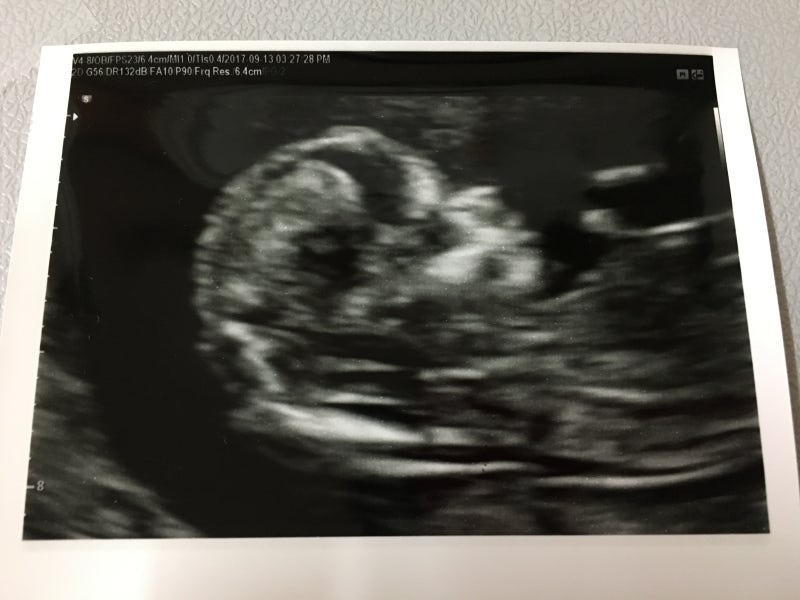

검사중 발길질 실력을 자랑하는 오토www

일단 1차 기형아 검사 초음파에서 제일 먼저 확인한 머리~꼬리뼈 길이www #임신 12주차 정도가 되면 6~7cm 정도 된다고 합니다. ^^

그다음에 본 뇌!# 임신기 형 검사를 통해서 뇌 초음파는 처음 봤는데 뇌가 나비 모양이었던데요? 다들 알고 계셨나요?되게 신기했어요.뇌가 나비 모양으로 잘 성장했는지 머리 옆 길이를 쟀어요.가로 길이는 2cm 정도 되네요. ~

그리고 그 유명한 #목 투명 대검사! 목 투명대가 너무 두꺼우면 다운증후군과 에드워드 증후군이 있을 확률이 높다고 합니다. 나무의 투명대는 3mm를 넘지 않아야 한다고 하는데 오토는 1.7mm로 통과했습니다. 후~

안녕하세요~ 해주는 오토 그리고 콧날이 잘 늘어나는지 확인해보는데 이것도 다운증후군과 관련이 있다고 합니다.다행히 코뼈도 잘 생겼네요.손가락도 딱 5개ㅋㅋㅋㅋㅋㅋㅋㅋㅋㅋㅋㅋㅋㅋㅋㅋㅋㅋㅋㅋㅋㅋㅋㅋㅋㅋㅋㅋㅋㅋㅋㅋㅋㅋㅋㅋㅋㅋㅋㅋㅋㅋㅋㅋㅋㅋㅋㅋㅋㅋㅋㅋ하하하하하하하하하하하하하하하하하하하하하하하하하하하하하하하하하하하하하하하.

1차 기형아 검사 중에 #12주 성별도 한번 봐주셨는데 다리 사이에 뭔가 삐걱거리는 게 존재감이 가득하죠?그래서 혹시 아들이에요? 그러면 탯줄일 수도 있고 손일 수도 있고 저게 없어질 수도 있다고 ㅋㅋㅋ 16주 지나서 보는 게 제일 정확하다고 했어요! 아들이든 딸이든 건강했으면 좋겠어요^^!

심장 박동도 확인해 주세요.153비트가 나왔는데 정상이래요(웃음)